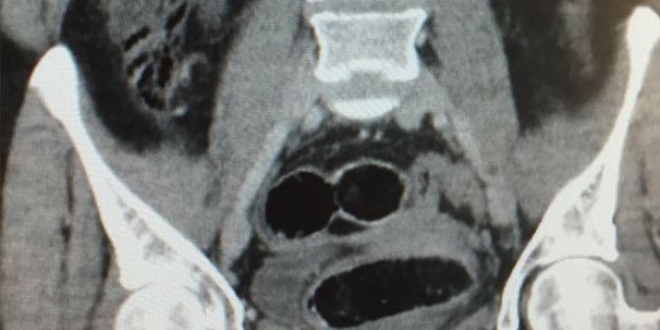

Şahısların hal ve hareketlerinden şüphelenen ekipler, şüpheliler üzerinde arama yaptı. Aramada şahıslar üzerinde uyuşturucu maddeye rastlamayan polis, şahısları gözaltına aldı. Gözaltına alınan şahıslar kontrol için Muş Devlet Hastanesine sevk edildi. Hastanede Rus uyruklu kadın N.O.'un çekilen röntgeninde yuttuğu anlaşılan 7 paket kalıp halinde eroin tespit edildi.

Öte yandan midede uyuşturucu taşımanın dünyada nadir görülen bir yöntem olduğu öğrenildi. Şahıslar hakkında adli işlemler devam ediyor.